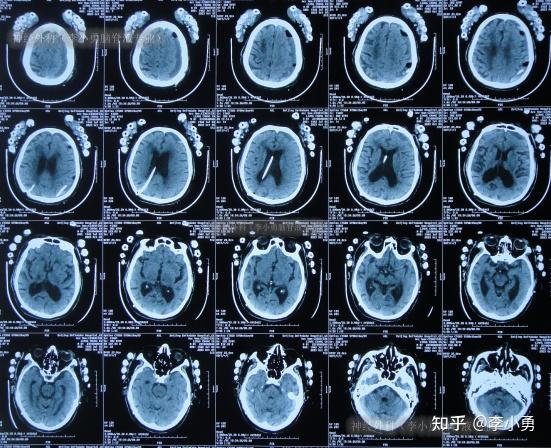

81岁老年脑积水腰大池分流术反致颅内感染颅内出血及走路不能2年余